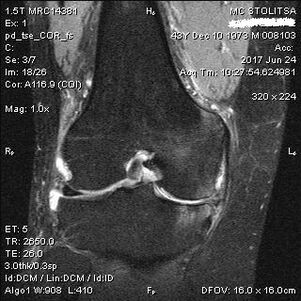

Діагностика артрозу колінного суглоба проводиться в кабінеті ревматолога або ортопеда. Лікар оглядає уражений суглоб, пальпує його, вислуховує скарги і задає додаткові запитання. Виконує кілька тестів - наприклад, просить пацієнта зігнути ногу або пройти кілька кроків. Потім, якщо необхідно уточнити стадію захворювання або характер патологічних змін, він направить вас на додаткові дослідження. Наприклад, для комп’ютерної томографії або рентгенографії.